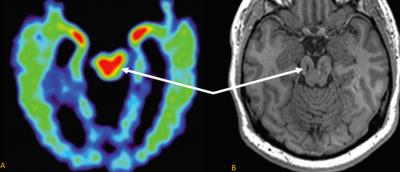

Using a new software tool for analyzing MRI scans, the researchers detected the shrinkage of several key brain regions in a former football player with cognitive problems. The same pattern of brain changes is commonly seen in CTE cases that have been confirmed by autopsies after a person's death.

The MRI scan did reveal a few small lesions consistent with Smith's history of brain trauma. Merrill and Raji also used a new FDA-cleared MRI software analysis tool called Neuroreader to measure the volumes of 45 different regions of the patient's brain.

The analysis revealed abnormally low volumes for Smith's brainstem, his ventral diencephalon and frontal lobes. The shrinkage in these volumes was worse in the later scan, suggesting a progression of disease. On the whole Smith's brain lost about 14 percent of its total gray-matter volume (the volume taken up by brain cells, not nerve fibers) during the four-year interval.

Researchers are trying to develop other methods for diagnosing CTE in the living, including PET scans based on radioactive tracers that bind to tau aggregates. But an MRI-based method, which uses no radioactive materials, would be safer and less expensive, Merrill said.